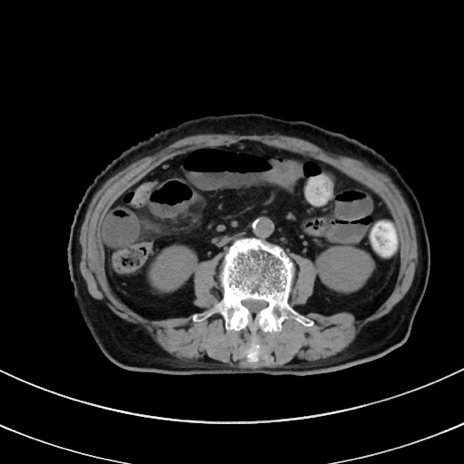

症例33(横断像)

【症例】70歳代 女性

【主訴】心窩部痛

【現病歴】延髄病変の精査・加療にて神経内科入院中。本日より心窩部痛あり。

【既往歴】虫垂炎

【身体所見】右下腹部を中心に圧痛と反跳痛あり。

【データ】WBC 10900、CRP 0.02